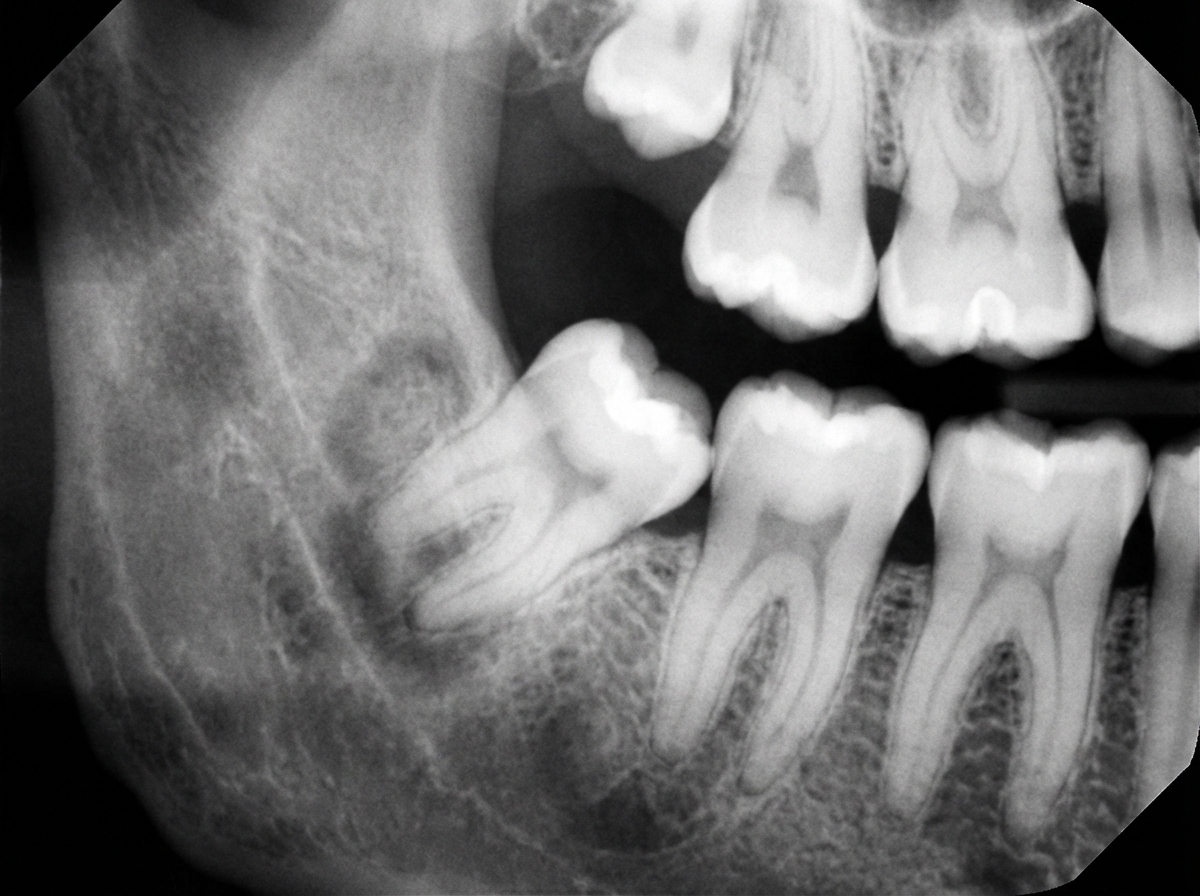

Which of the following interpretations cannot be associated with the given radiograph?

Explanation: ***Periapical cemental dysplasia*** - This is a **fibro-osseous lesion** that occurs at the **apex of vital, normally erupted teeth**, typically mandibular incisors and canines, not impacted molars. - It involves **vital teeth with normal pulp** and has no association with **impacted third molars** or their complications. *Recurrent pericoronitis* - Common complication of **impacted third molars** where the **operculum** (gum flap) becomes inflamed and infected. - Radiographically shows **impacted tooth** with possible **bone loss** around the crown area and **radiolucent areas** indicating infection. *Peripheral sclerosing osteitis* - Also known as **condensing osteitis**, it appears as **radiopaque sclerotic bone** around infected or impacted teeth. - Commonly seen around **impacted third molars** as a **reactive bone formation** in response to chronic low-grade infection. *Impacted 3rd molar* - Clearly visible on radiographs as a **tooth that has not erupted** into its normal position. - Shows the **crown and root formation** of the wisdom tooth trapped beneath the **second molar** or **alveolar bone**.

Explanation: **Explanation:** The correct answer is **Dentigerous cyst** (also known as a follicular cyst). This is the most common type of non-inflammatory odontogenic cyst. **Why it is correct:** A dentigerous cyst originates from the separation of the **follicle** (reduced enamel epithelium) from around the crown of an **unerupted tooth**. Radiologically, it presents as a well-defined, unilocular **radiolucency** attached to the cemento-enamel junction (CEJ) of a completely formed but unerupted tooth. The most common sites are the mandibular third molars and maxillary canines. **Why other options are incorrect:** * **Impaction:** This refers to the clinical state where a tooth fails to erupt into the dental arch within the expected time. While a dentigerous cyst is associated with an impacted tooth, "impaction" itself is a condition, not the cause of the radiolucency. * **Periodontal cyst:** These are typically inflammatory in nature (e.g., periapical/radicular cyst) and are associated with the apex of a **non-vital, erupted tooth**, rather than an unerupted one. * **Odontogenic cyst:** This is a broad category that includes dentigerous cysts, keratocysts, and radicular cysts. While a dentigerous cyst *is* an odontogenic cyst, "Dentigerous cyst" is the most specific and accurate diagnosis for a radiolucency surrounding an unerupted crown. **High-Yield NEET-PG Pearls:** * **Radiological Hallmark:** A radiolucency larger than 3-4 mm surrounding the crown of an unerupted tooth is suggestive of a cyst rather than a normal dental follicle. * **Attachment:** The cyst always attaches at the **cemento-enamel junction (CEJ)**. * **Potential Complications:** If left untreated, it can lead to bone expansion, root resorption of adjacent teeth, or rarely, transform into an Ameloblastoma or Squamous Cell Carcinoma.